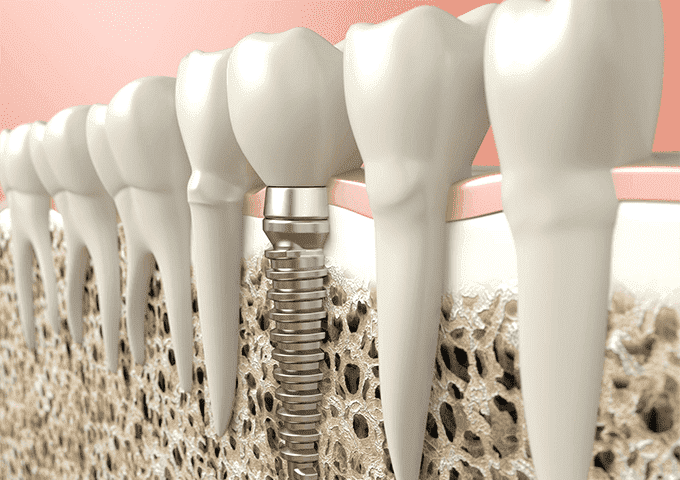

今まで見ることができない部分が立体的に、かつ詳細に確認できるので、精度の高い診断、綿密な治療計画の立案、安全な治療が 可能です。

特に、インプラント治療では、歯と顎の骨の位置関係、大きさなど 従来のレントゲンでは見ることのできない情報が安全性において特に重要 です。